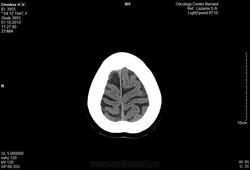

Женщина 64-х лет.

Диагноз:

Метостаз в правой теменной кости без первичного очага.Предложена лучевая терапия. Описание снимка: форма и размеры черепа обычные, в теменной кости определяется деструкция костной ткани без четких контуров размером 16мм.

Замыкательные пластинки истончены. Определяется снижение пневмотизации правой гайморовой пазухи за счет утолщения слизистой, слева на нижней стенке гиподесное образование с ровными контурами размером 22мм. Вещество мозга однородной структуры в симметричных участках плотность одинаковая. Среденные образования не смещены. Определяется неравномерное расширение субарахноидальных пространств и усиление борозд больше в лобных и теменных областях.

Заключение:

Наружная гидроцефалия, метостаз в теменную кость, киста левой гаиморовой пазухи, гайморит справа.

///верно ли оно?/// Признаков гидроцефалии нет никаких, непонятно на основании чего поставлен гайморит справа, киста в левой верхнечелюстной пазухе есть. По этим снимкам (в этом режиме/окне) оценить состяние костей не представляется возсожным. Скопируйтк с диска dicom-изображения, сархивируйте их, разместите на любом файлообменнике, разместите здесь ссылку. Тогда можно будет посмотреть детальнее.

Согласна, в головном мозге - норма. Кости не показаны, надо смотреть. Гайморит сомнителен, надо смотреть в костном режиме.

Наружная гидроцефалия явно надумана за счет верхних нормальных для возраста срезов, а метастаз в кости не определяется в данном окне.

По этим снимкам невозможно оценить, что там в костях. Нужен DICOM. В мозге - умеренная атрофия, соответствующая возрасту.